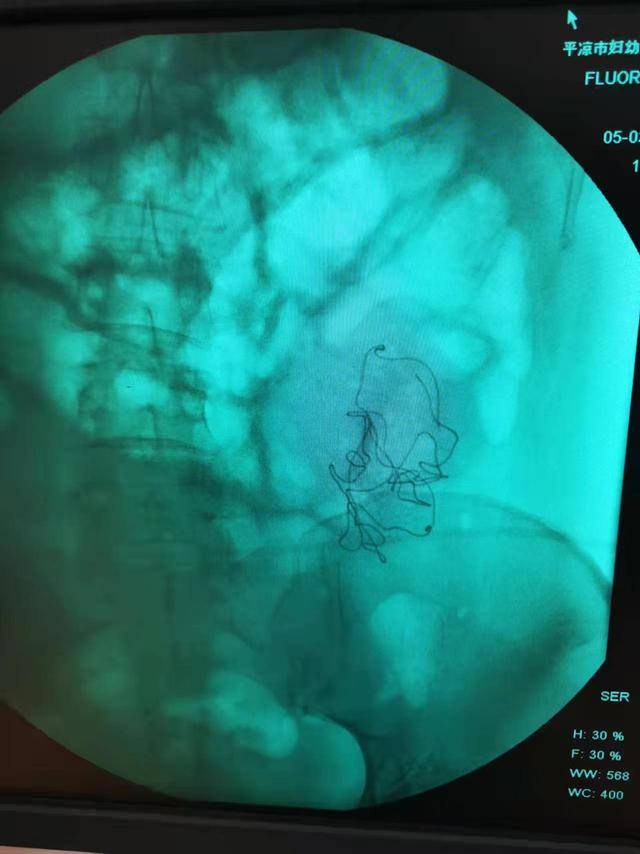

在秦红利多次请求下,院方终于将当时的检查影像交给了她。影像中,腹腔内异物影清晰可见。然而,在当天的手术记录中,这一异常没有留下任何痕迹。

秦红利分娩后,进行X光检查发现异物清晰可见。本文图片均为 受访者供图

手术记录中,二次开腹的原因是腹腔渗血,并写道:“因病情紧急在产房行急诊剖宫产术,为确保病人安全急行X线透视以观察腹腔内情况,X线透视显示有少量液平面,考虑血管收缩渗血可能,遂入手术室在静脉麻下行腹腔探查,发现腹膜一小血管渗血立即缝扎止血,再次探查腹腔无异常遂常规关腹”。